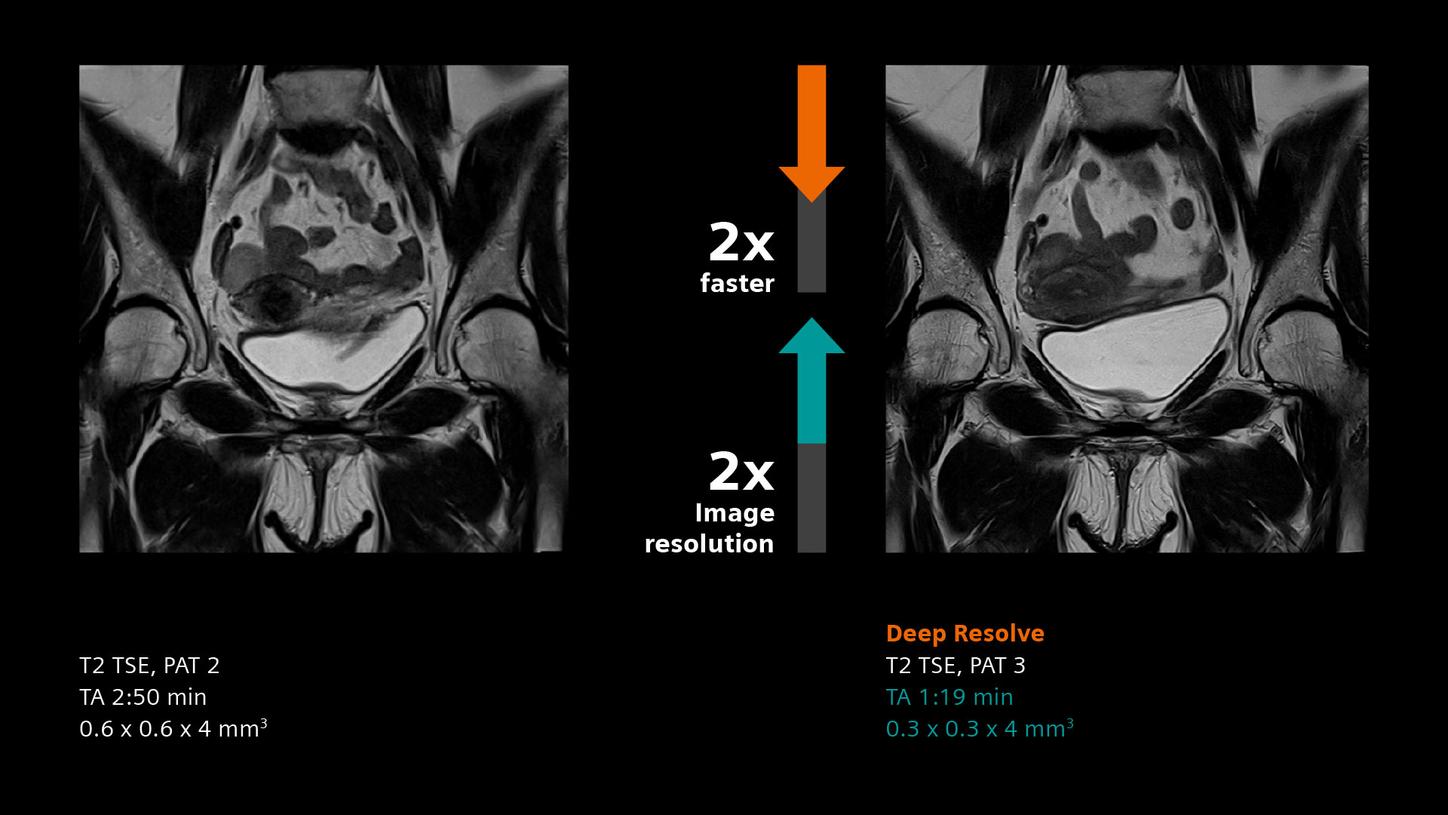

Deep Resolve will be at the forefront of the revolution in MRI acceleration. Deep Resolve will enable our fastest MRI, with images that will have extraordinary clarity, higher clinical productivity, and an even better patient experience. This transformational effect of Deep Resolve is now planned to expand to 3D5, unlocking a new dimension in MRI image resolution and speed.